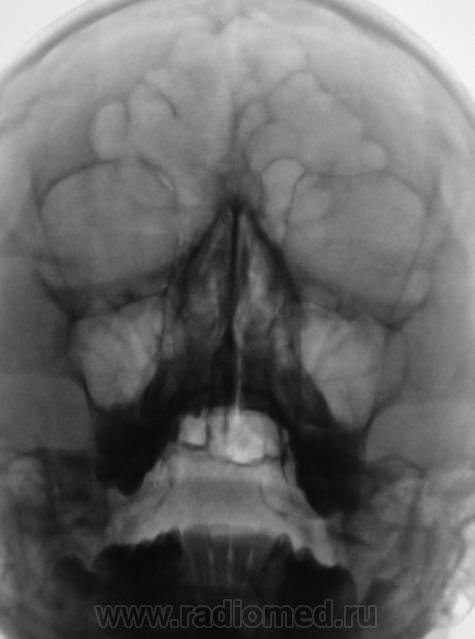

ДОБРЫЙ ВЕЧЕР! Объёмное образование левой в/ч пазухи - неуточнённого х-ра (на кисту не очень смахивает,хотя кто его знает, но деструкцию стенок пазухи не вижу).Рекомендую , банально сделать КТ или МРТ, если нет возможности -наблюдайте (повтор я бы назначил ч/з 1,5 мес).Справа - вн/отделах у-нь жидкости.

ДОБРЫЙ ВЕЧЕР! Объёмное образование левой в/ч пазухи - неуточнённого х-ра (на кисту не очень смахивает,хотя кто его знает, но деструкцию стенок пазухи не вижу).Рекомендую , банально сделать КТ или МРТ, если нет возможности -наблюдайте (повтор я бы назначил ч/з 1,5 мес).Справа и слева - в н/отделах у-нь жидкости.

А где увидели кисту и какие признаки новообразования - я не нашел...

Мне как то тоже не думается, что это киста, от права отличается только полоской "просветления" форма просвета пазух, кажется практически идентичная..может какая аномалия развития альвеолярного отростка?

Двусторонний гайморит (пристеночная киста слева в ст. формирования).

Но что касается одностороннего пристеночного процесса - это однозначно ДА!

По данной рентгенограмме уточнить его форму, структуру, полное отношение к стенке нереально.

Нормальнейшая норма+игра теней.

Если были сомнения, надо было доснять носолобную проекцию.